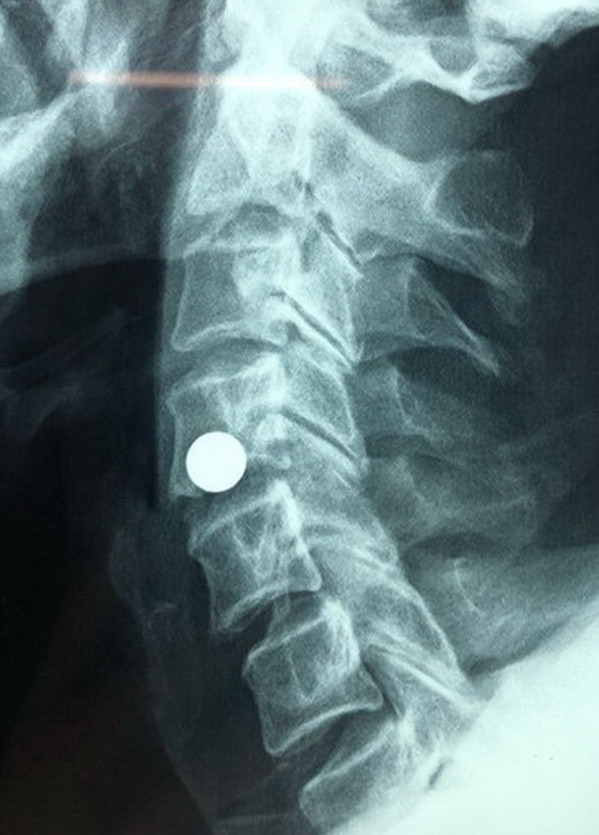

Cần Thơ: Cứu sống bệnh nhân bị đạn bi găm vào cột sống cổ ảnh 2Chụp X-quang phát hiện dị vật. (Ảnh: TTXVN phát)

Các bác sỹ tiến hành hội chẩn hình ảnh và thống nhất chẩn đoán: có ngoại vật bằng kim loại nằm mặt trước bên trái khoảng đốt sống C4-5; chèn vào lỗ liên hợp C4-5 bên trái gây tổn thương động mạch đốt sống và rễ thần kinh bên trái. Bệnh nhân được chỉ định phẫu thuật cấp cứu lấy dị vật và xử trí tổn thương.

Sau 1 giờ phẫu thuật, một viên bi sắt đường kính 8 mm nằm cạnh bên trái của khí quản và thực quản đã được các bác sỹ lấy ra.

Viên bi sắt này chính là nguyên nhân gây chèn ép động mạch đốt sống cổ và rễ thần kinh cổ bên trái của bệnh nhân.